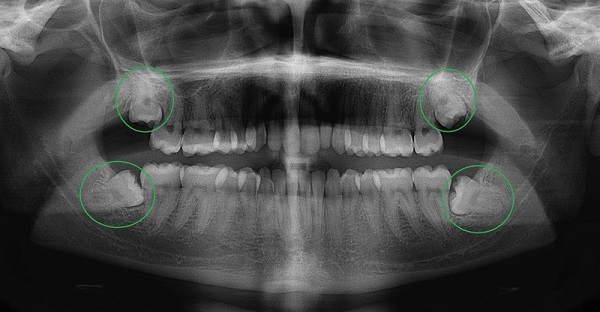

Chụp X quang toàn cảnh răng (chụp Panorama răng)

Đây là phương pháp chụp X quang được sử dụng để kiểm tra toàn bộ khoang miệng. Bằng cách sử dụng kỹ thuật chụp cắt lớp vi tính, nha sĩ có thể thấy rõ răng và mô xương. Trong quá trình chụp, bệnh nhân sẽ được bảo vệ bằng áo chì và cố định trên máy để thu được hình ảnh sắc nét của răng và xương hàm dưới.

Hình ảnh Panorama răng là một công nghệ chụp X quang cho thấy rõ về xương hàm trên và dưới, các thành phần lân cận như khớp thái dương hàm, xoang mũi. Kỹ thuật này cũng cho phép bác sĩ nhìn thấy toàn bộ hai cung răng trên một phim giúp chẩn đoán nhiều loại bệnh lý răng miệng như răng mọc lệch, răng mọc ngầm, u nang, áp xe và tổn thương xương hàm.

Ưu điểm của kỹ thuật Panorama răng là thời gian chụp nhanh, hình ảnh chất lượng cao, an toàn và phù hợp với mọi đối tượng, bao gồm cả trẻ em – nhóm khách hàng khó chụp X quang bằng các phương pháp truyền thống. Tuy nhiên, điểm trừ của phương pháp này là không phát hiện được những vấn đề như lỗ sâu răng, gãy xương, nhiễm trùng,…

Chụp X quang toàn cảnh răng tiện lợi